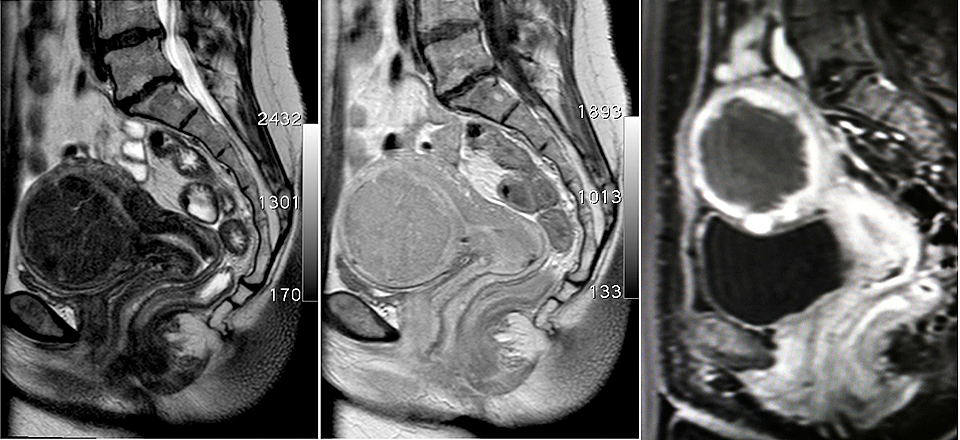

MR-Bilder die ein großes Gebärmuttermyom anzeigen MR-Bilder die ein großes Gebärmuttermyom anzeigen

MR-Bilder vor (linkes und mittleres Bild) zeigt ein großes Gebärmuttermyom. Unmittelbar nach der MR-gesteuerten HIFU-Behandlung (rechtes Bild) ist das Myom zentral nicht mehr durchblutet (dunkel dargestellt)